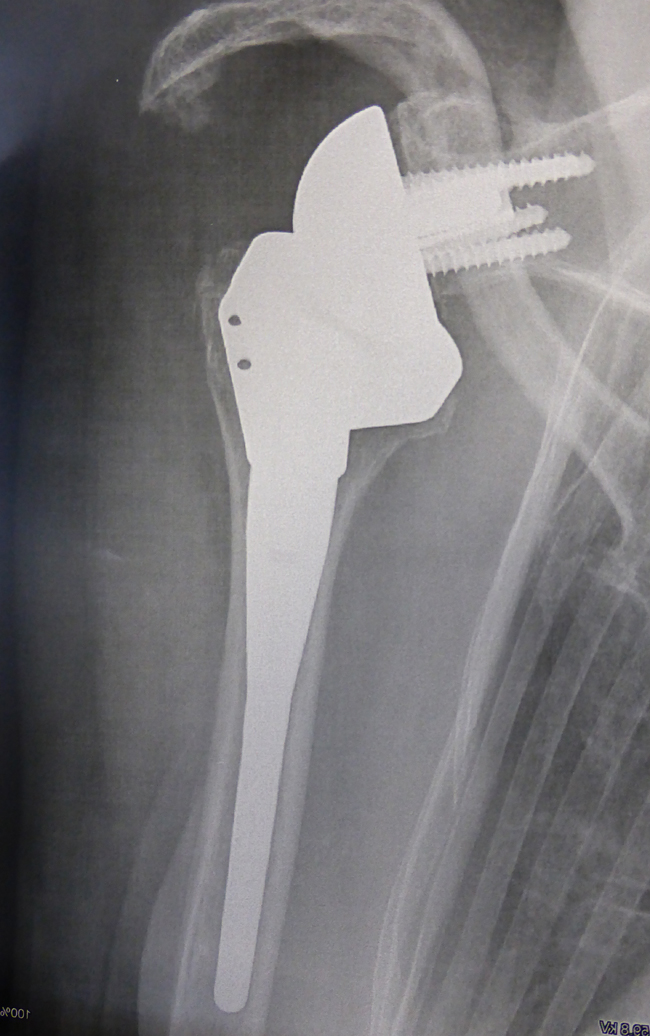

- Les prothèses totales inversées inversent la forme originale des surfaces articulaires :

- Sur l’humerus par un composant en polyéthylène concave

- Sur l’omoplate par un composant métallique convexe

Ces prothèses inversées sont indiquées lorsque les tendons de la coiffe sont rompus ou inefficaces.

Les prothèses inversées ont prouvé leur efficacité en particulier dans les situations suivantes :

- Rupture de coiffe étendue

- Polyarthrite rhumatoïde

- Complications de prothèses d’épaule anatomiques

- Séquelles de fractures complexes

- Et même sur coiffe intacte chez les sujets très âgés dans certains cas.

Ces prothèses donnent habituellement de très bons sur les douleurs et permettent de retrouver l’élévation du bras.

Les mouvements de rotation active (mains derrière le dos ou main sur la tête) sont plus difficiles à retrouver, notamment en cas de rupture complète de tous les muscles de la coiffe des rotateurs.